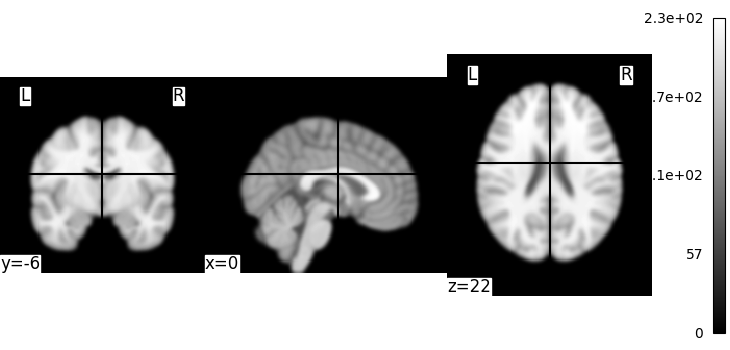

This is an in-memory object. We can pass it to nilearn function, for instance to look at it

We could also pass it to the smoothing function

<nilearn.plotting.displays._slicers.OrthoSlicer object at 0x7f36fac471f0>